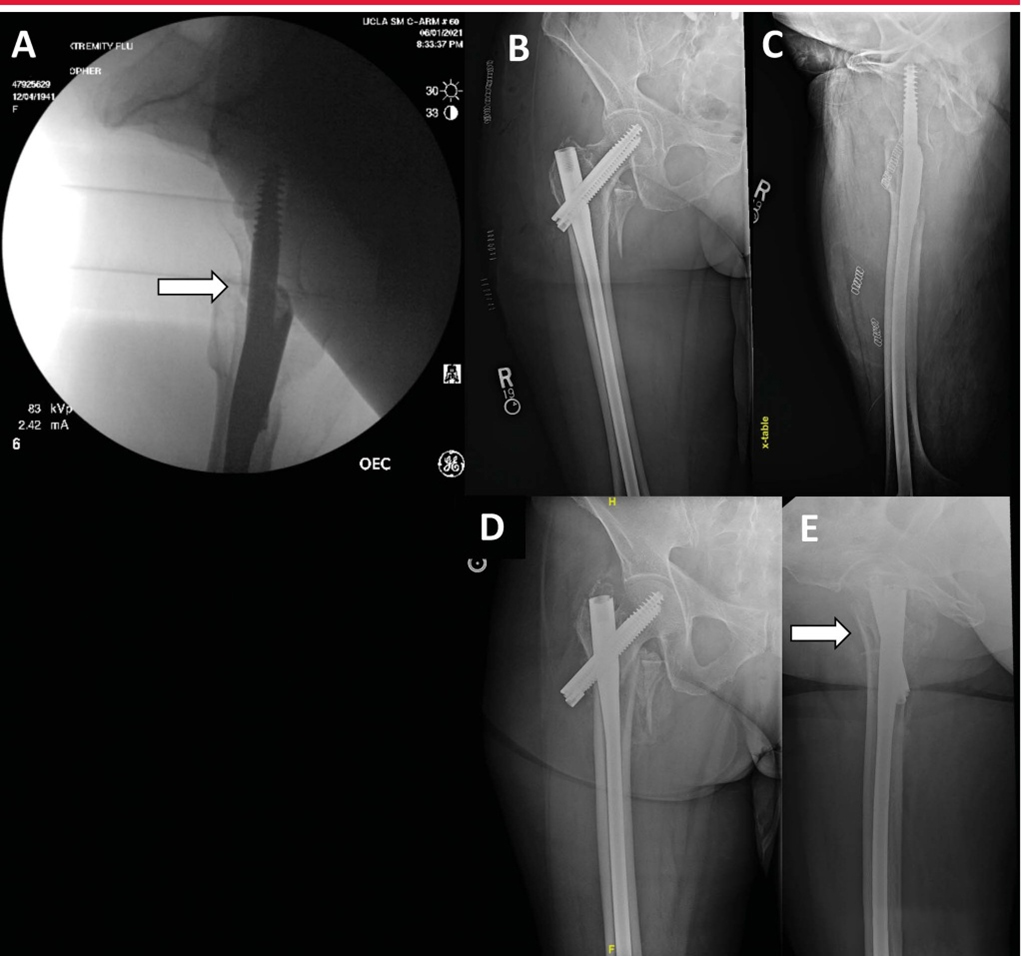

Вид с боковой редукцией показывает переднемедиальную кортикальную поддержку (стрелка). B: Послеоперационное AP-изображение, показывающее выравнивание кортикального слоя. C: Послеоперационное боковое изображение демонстрирует деформацию переднемедиальной кортикальной опоры. D-E, AP и боковые проекции показывают значительный коллапс (стрелка) через 6 недель после операции.

Латеральная анатомическая репозиция может быть затруднена, возможно, из-за сильных ограничений подвздошно-бедренной связки. Предотвращает смещение шейки бедра вперед. Техника, которую можно использовать, заключается в размещении спиц Шанца спереди назад вдоль медиальной и нижней части шеи. Это позволяет поднять переднемедиальную кортикальную опору до анатомической редукции и/или положительной редукции.